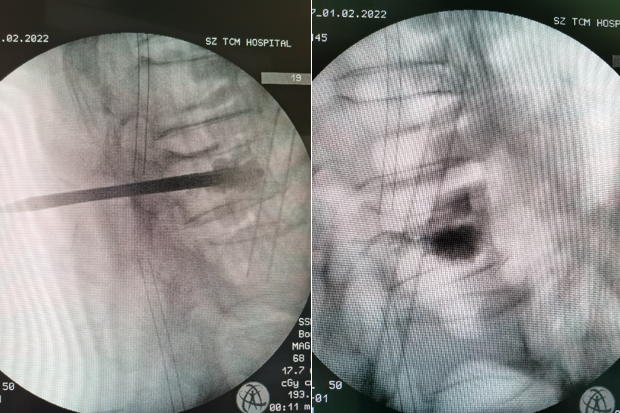

急查胸腰椎MRI提示腰2椎体新鲜压缩性骨折,需要手术治疗。和手术室沟通后于10:30送手术室在麻醉医生普玉菊、巡回护士赵静、器械护士余正强的积极配合下半小时完成手术。

术中精准定位注入拉丝期骨水泥,骨水泥充分弥散。术后患者疼痛即刻缓解。患者非常满意,并表示这是新春最好的礼物。